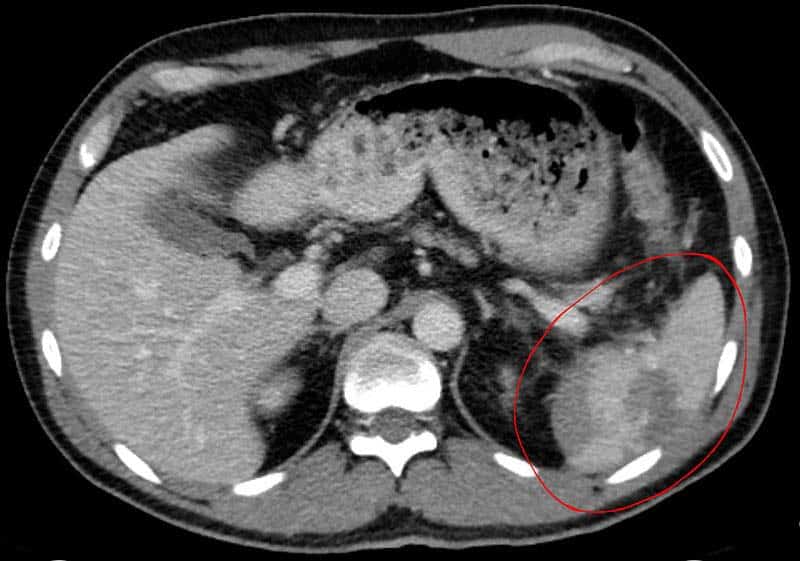

The spleen is an organ located in the upper left abdomen, and is roughly the size of a clenched fist. In the adult, the spleen functions mainly as a blood filter, removing old red blood cells. It also plays a role in both cell-mediated and humoral immune responses. In this article, we shall look at the anatomy of the spleen – its anatomical position, structure and vasculature. By TeachMeSeries Ltd (2025) Fig 1The anatomical position of the spleen in the abdomen. Pro Feature - 3D Model You've Discovered a Pro Feature Access our 3D Model Library Explore, cut, dissect, annotate and manipulate our 3D models to visualise anatomy in a dynamic, interactive way. Learn More Anatomical Position The spleen is located in the upper left quadrant of the abdomen, under cover of the diaphragm and the ribcage – and therefore cannot normally be palpated on clinical examination (except when enlarged). It is an intraperitoneal organ, entirely surrounded by peritoneum (except at the splenic hilum). The spleen is connected to the stomach and kidney by parts of the greater omentum – a double fold of peritoneum that originates from the stomach: Gastrosplenic ligament – anterior to the splenic hilum, connects the spleen to the greater curvature of the stomach. Splenorenal ligament – posterior to the splenic hilum, connects the hilum of the spleen to the left kidney. The splenic vessels and tail of the pancreas lie within this ligament Between these two ligaments is the lesser sac. By TeachMeSeries Ltd (2025) Fig 2The ligaments of the spleen. Note how the splenic vessels run within the splenorenal ligament. Pro Feature - Dissection Images Dissection of the visceral surface of the spleen. Note how the splenic artery divides into five branches - – each supplying vascular segment of the spleen, Dissection of the visceral surface of the spleen. Note how the splenic artery divides into five branches - – each supplying vascular segment of the spleen, You've Discovered a Pro Feature Access our Dissection Image Library Enhance your understanding with high-resolution dissection images showcasing real-life anatomy. Learn More Structure The spleen has a slightly oval shape. It is covered by a weak capsule that protects the organ whilst allowing it to expand in size. The outer surface of the spleen can be anatomically divided into two: Diaphragmatic surface – in contact with diaphragm and ribcage. Visceral surface – in contact with the other abdominal viscera. It has anterior, superior, posteromedial and inferior borders. The posteromedial and inferior borders are smooth, whilst the anterior and superior borders contain notches. In enlargement of the spleen (known as splenomegaly), the superior border moves inferomedially, and its notches can be palpated. Anatomical Relations It lies in close proximity to other structures in the abdomen: Anterior Posterior Inferior Medial Stomach Diaphragm Left lung Ribs 9-11 Left colic flexure (splenic flexure) Left kidney Tail of the pancreas Vasculature The spleen is a highly vascular organ. It receives most of its arterial supply from the splenic artery. This vessel arises from the coeliac trunk, running laterally along the superior aspect of the pancreas, within the splenorenal ligament. As the artery reaches the spleen, it branches into five vessels – each supplying a different part of the organ. These arterial branches do not anastomose with each other – giving rise to vascular segments of the spleen. This enables a surgeon to remove one of these segments without affecting the others (a procedure known as a subtotal splenectomy). Venous drainage occurs through the splenic vein. It combines with the superior mesenteric vein to form the hepatic portal vein. By TeachMeSeries Ltd (2025) Fig 3An overview of the venous portal system – draining into the hepatic portal vein. Innervation The nerve supply to the spleen is from the coeliac plexus. Lymphatics The lymphatic vessels of the spleen follow the splenic vessels mentioned above and drain into the pancreaticosplenic lymph nodes, and ultimately the coeliac nodes. Clinical Relevance Rupture of the Spleen The spleen is the abdominal organ with the highest incidence of injury. A splenic rupture occurs when there is a break in its fibroelastic capsule, disrupting the underlying parenchyma. Rupture is caused by blunt or penetrating trauma. It is often associated with left rib fractures, with a bony fragment easily tearing the capsule. As the spleen is a highly vascular organ, its rupture results in profuse bleeding into the peritoneal cavity. Splenectomy is indicated where injury to the spleen and subsequent haemorrhage are life threatening. This may be done as a sub-total (partial) splenectomy – recall that there are no arterial anastomoses in the spleen – or as a total splenectomy. The liver and bone marrow take over some of the functions of the spleen, however, an individual who has no spleen is more susceptible to some bacterial infections and as such, requires life long antibiotics. Further indications for splenectomy include haematological conditions such as haemolytic anaemia, idiopathic thrombocytopenic purpura, thrombotic thrombocytopenic purpura, hypersplenism and prolieferative disorders such as myelofibrosis of lymphoma. By Hellerhoff [CC-BY-SA-3.0], via Wikimedia Commons Fig 4CT scan of a ruptured spleen. Do you think you’re ready? Take the quiz below Pro Feature - Quiz The Spleen Question 1 of 3 Submitting... Skip Next Rate question: You scored 0% Skipped: 0/3 1800 More Questions Available Upgrade to TeachMeAnatomy Pro Challenge yourself with over 1800 multiple-choice questions to reinforce learning Learn More Rate This Article